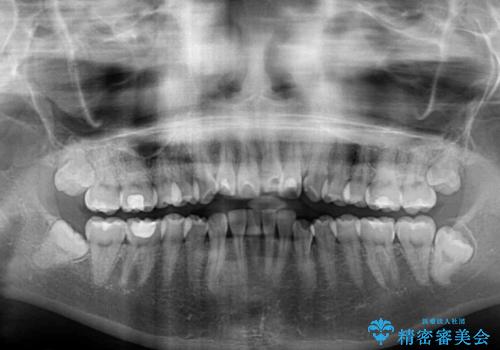

- デコボコと飛び出した前歯を治したいとのことで来院された患者様です。

ゴムかけを活用して上顎歯列全体を後方移動し、IPR(歯と歯の間を削る)によってデコボコが解消するように設計し、インビザラインにより治療を行うこととしました。

後方移動に際し、上下顎の親知らずは4本とも抜歯することとしました。